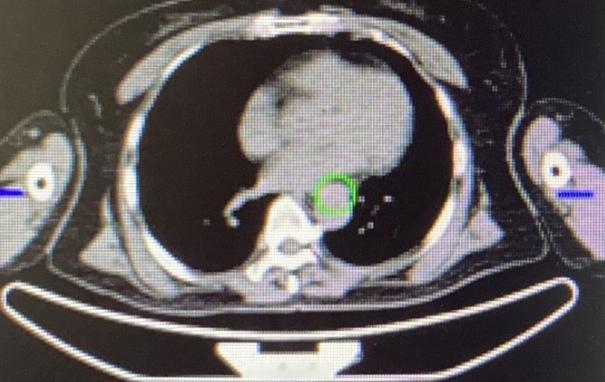

门诊一位65岁的农村阿姨,真的特别有健康意识!虽然身体一直挺硬朗,但她每年都会主动做胃镜检查。她父亲当年七十多岁因为食管癌去世,这件事她一直记在心里。 阿姨跟我说:“乔医生,我们农村人懂得不多,但听人说这个病有遗传的可能,我就上了心。每年不查一次,心里就不踏实,觉都睡不好。” 其实家里孩子不太理解,觉得她太紧张、浪费钱,可她就是坚持自己的习惯。 结果今年胃镜查出来,食管上有个小溃疡,阿姨自己上网查资料,看到我的科普,马上就来门诊找我了。后来取了活检,证实确实是早期食管癌。 幸运的是,全身检查下来没有发现转移,肿瘤也非常小,完全可以手术切除。 我们给她做了胸腹腔镜联合的微创手术,创伤小、恢复快。手术第二天,阿姨就能自己下床活动了,精神状态很好。 这件事让我特别感慨:肿瘤不怕发现得早,就怕发现得晚。早发现、早处理,不仅效果好,病人恢复也快,甚至能达到根治。 所以说,健康这件事,多一分谨慎总是好的——这位阿姨的“谨慎”,真的救了她自己。[作揖][玫瑰]